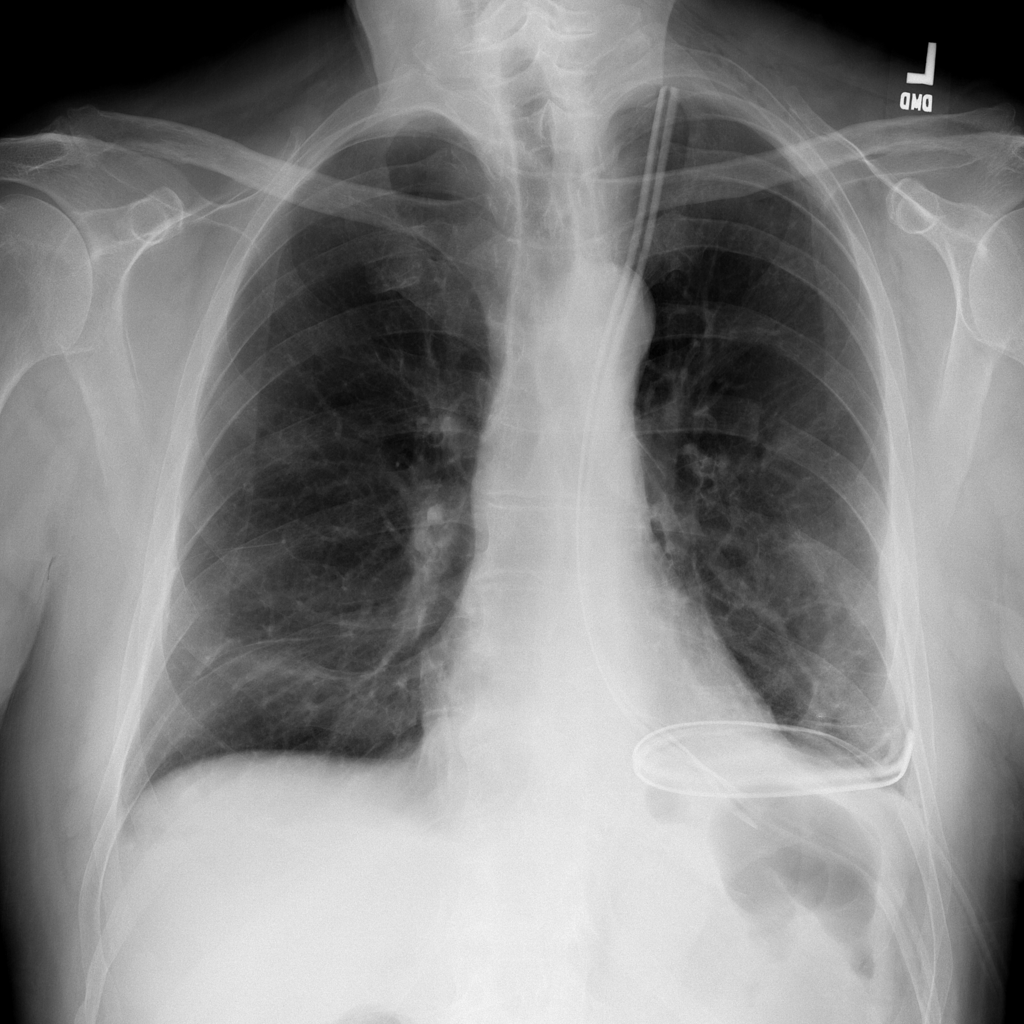

PAT-B0DB · IMG-003Emphysema

PAT-B0DB · IMG-003

PA